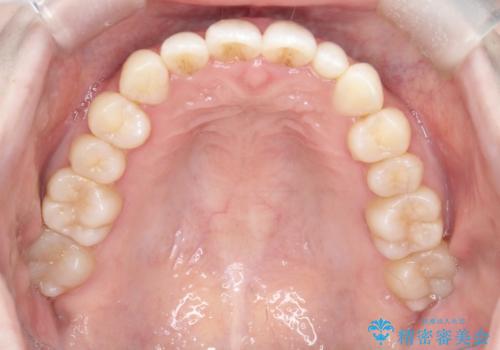

【インビザライン】矮小歯を有する方の治療②

- 前歯の凸凹を主訴に来院されました。

左上の前歯が元々小さいため、前歯の真ん中が揃わないことを伝えた上で矯正治療を開始しています。

スペースを作るために遠心移動ろIPRをおこなて治療を行いました。